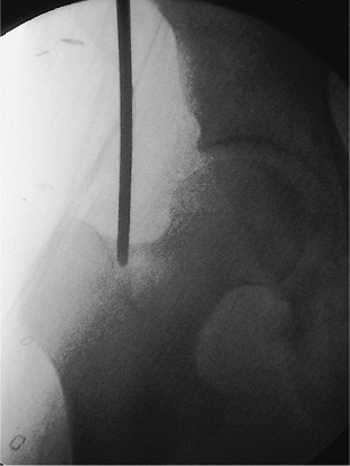

A guide pin is placed in the piriformis fossa, and its position is

confirmed with fluoroscopy. The tip should be centered directly in-line

with the medullary canal as seen in both the AP and lateral views.

Medial portal placement should be avoided because it may cause a

femoral-neck fracture. Portal placement laterally may lead to

comminution and varus alignment in proximal fractures. Once the pin is

properly positioned in the piriformis fossa and is confirmed

fluoroscopically, the femur is opened with a cannulated drill. In an

alternative, an awl may be placed in the piriformis fossa and the

proximal femur opened by hand (Figs. 21.12,21.13,21.14,21.15,21.16,21.17,21.17,21.18,21.19,21.20)

![]() |

|

Figure 21.12.

Femoral entry-portal establishment with Kuntscher awl. In an alternative technique, a curved awl can be used for establishing an entry portal in the proximal femur (A). Initial position of the awl established by digital palpation should be confirmed radiographically with the c-arm. The AP and lateral views should include images of the greater trochanter, femoral head, and the proximal portion of the medullary canal (B). The surgeon should imagine a line passing down the center of the medullary canal and projecting out the top of the femur (C). The entry portal should be established exactly where this line emerges in the AP view (D). |

Figure 21.13.

Femoral entry portal establishment with cannulated drill. As shown here, a 5/32 inch Steinmann pin is guided radiographically and drilled into the piriformis fossa. |